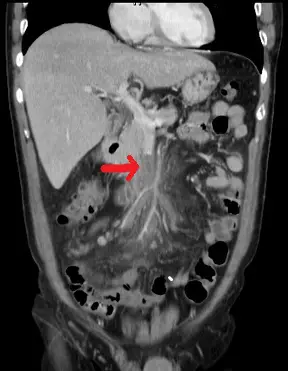

56歲男性病患,過去有高血壓病史,突然有發燒、嘔吐與腹痛的症狀,緊急安排了電腦斷層檢查影像如附圖,下列何者為最可能的診斷?

影像分析:

冠狀位增強CT掃描中,紅色箭頭所指為superior mesenteric vein主幹及其多條分支,內見中心低密度充填缺損,周邊血管壁呈環狀增強。小腸壁輕度增厚,周圍mesenteric fat stranding明顯,代表靜脈回流阻塞所致水腫與發炎。未見主動脈內膜剝離徵象,也無盲腸或結腸局部憩室病變,影像特徵高度指向SMV栓塞。

- 選項C 上腸繫膜靜脈血栓:符合SMV充填缺損、中心低密度、周邊環狀增強,並伴mesenteric fat stranding、小腸壁水腫;病人嘔吐、發燒、腹痛亦為SMVT高頻臨床表現,為最佳診斷。